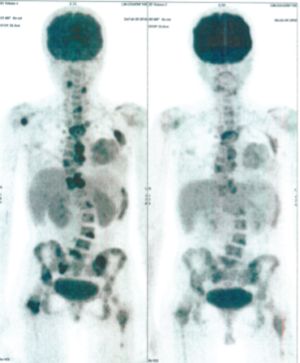

Below are some of the cases, from more than 80 cases we have treated so far with good results. When reading the PET/CT scans, the picture on the left is before treatment, and the picture on the right is after treatment. The intensity of black represents the activity of the cancer, but some black areas are not cancer: brain, heart, radioactive urine in bladder. For the heart, the intensity of black depends on the number of hours of fasting: if more than 10 hours, the heart is not even black, but if fasting is less than 6 hours, it is very black. The intensity of black in the brain can be variable in different scans depending on the brain activity at the time of the scan. The intensity of black in the radioactive urine can also be variable due to the hydration of patients and the time of injection of diuretic.

CASE NO: 1

(HEPATOCELLULAR CARCINOMA + STOMACH CANCER)

A middle-aged women who is very thin and very weak, can hardly walk, lying in bed most of the time. She saw a cancer specialist in a top hospital who discovered that she had massive hepatocellular carcinoma, and another cancer in the stomach. Given that hepatocellular carcinoma is incurable and stomach cancer is very difficult if not impossible to cure without surgery, she was told that nothing could be done for her. She came to ask us to help her. After just 4 treatment, the hepatocellular carcinoma went into remission, and the stomach cancer (arrow) became less active. Until today, more than 6 months later, the hepatocellular carcinoma is still in remission.